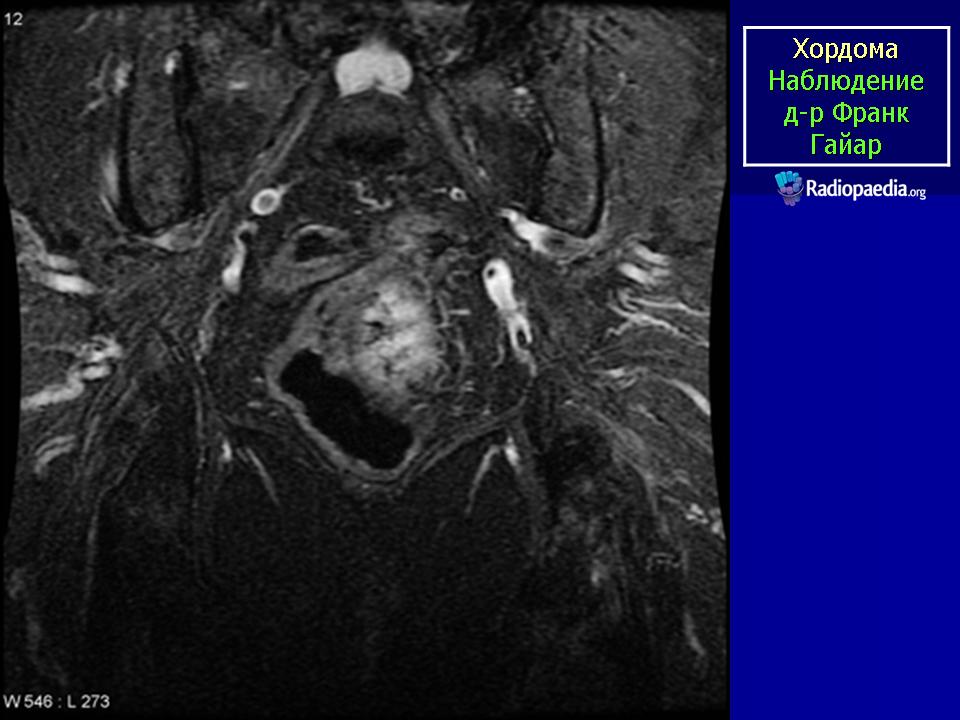

МР-изображения показывают большую гетерогенную твердую разрушающую массу, включающую большинство крестца и копчика, характерные для хордомы

Хордома крестца.

Случай 2: sacrococcygeal

Случай 7: sacrococcegeal

Случай 8: sacrococcygeal